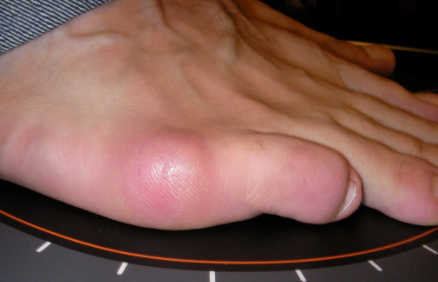

Juanete de Sastre

Juanete de Sastre: antes Juanete de Sastre: después